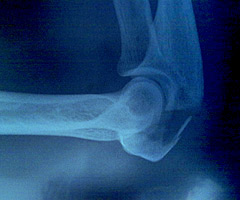

Pooperacni kontrola byla velmi uspesna. Kloub v lokti krasne srostl a ja jsem od lekare dostala zelenou.Velmi mne to potesilo. Konecne mohu opet sportovat.A draty se sroubama se budou, misto v zari, vyndavat nejspis jiz v breznu.:-)

gute Nachricht nach dem Arztbesuch in Zürich. Die Heilung geht schnell voran, darf bereits wieder mit dem Training beginnen, das Metall wird bereits im Frühling entfernt. Der Draht um die Knochen ist genau an der Stelle der Armauflage des Aerolenkers, (da muss man etwas basteln)

10.09.2010      Operace se vydarila       / Op ist gut verlaufen

Bohuzel musela byt ma, velmi dobre rozbehnuta sezona, predcasne ukoncena, z duvodu urazu na kole. V temer 50 km/hod jsem sklouzla na kolejich a uz vse letalo. Nastesti v nestesti to odnesl loket na leve ruce, jakozto levacka idealni, kde je kloub zlomeny, roztristeny. A k tomu pekne popaleniny od asfaltu, rozlicnych hloubek a velikosti. Hlava a zuby jsou tam kde maji byt, bez jakychkoliv sramu a nasledku. Nyni prede mnou stoji operace a relaxace a pak fyzioterapie. V kazdem pripade, zadny sport v pristich mesicich.Proste PAUSA. Zdravi vsechny fandy Ladka

das ist etwas für die Knochenschrauber